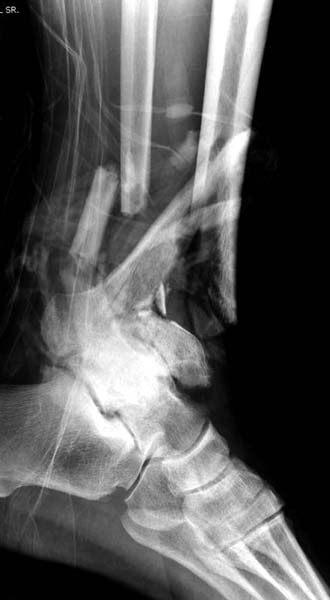

Современную тактику лечения переломов пилона описали коллеги, а мне остается подтвердить клинически. В многоэтапном лечении главное - это предупреждение сокращения мягких тканей, от которого зависит судьба конечности. Дистракция любым наружным фиксатором, и по готовности мягких тканей - премежуточная или окончательная фиксация.

В нашем случае, травма в результате коллапса крыши. Открытый перелом. Ургентные Irrigation and Debridment, дистракция наружным фиксатором. В госпиталях первого уровня редко бывает изолированная травма, и на другой стороне повреждение стопы с переломом навикулярной кости. После обработки раны - вакуум и двухсторонние наружные фиксаторы.

Вначале нет смысла заказывает КТ, только дистракция организует на свое место свободных фрагментов. По топографии отломком преоперационный план, а готовность мягкой ткани подтвердит появившиеся морщины на поверхности кожи, “Wrinkle Sign”.

Трудно предсказать, что в течение именно двух недель решится готовность к операции. Все зависит от энергии травмы, иногда образование морщин ждали более чем две недели. Любая интервенция без подготовки кожных покровов - это риск осложнений!